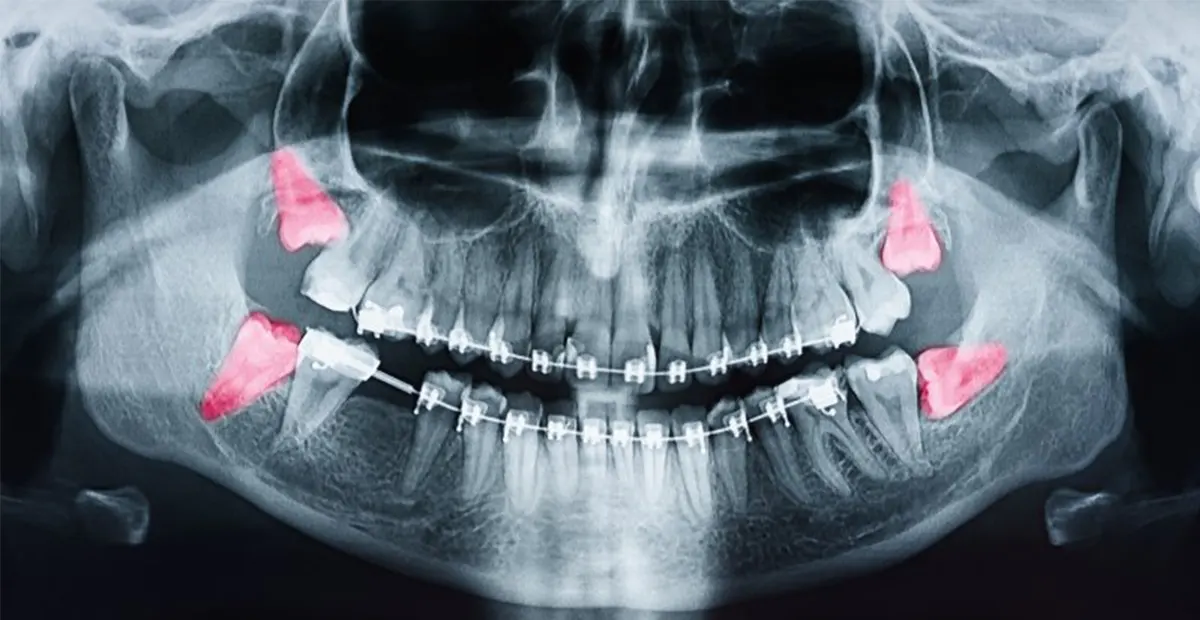

این دندانها (و به طور کلی تمامی دندانهای دیگر) میتوانند به روش معمولی یا به صورت جراحی کشیده شوند. دندانپزشک پس از بررسی تصاویر رادیوگرافی مانند OPG (نمای پانورامیک فکها) یا پریاپیکال (نمای دقیق ناحیهای) مشخص میکند که کدامیک از این دو روش برای بیرون کشیدن دندان شما مناسبتر است. بررسی وضعیت دندان عقل قبل از کشیدن یا جراحی بسیار مهم است. تصاویر پانورامیک (OPG) نمای کلی فک و دندانها را نشان میدهند و برای شناسایی دندانهای نهفته و زاویه رشد آنها مفید هستند. تصاویر پریاپیکال جزئیات دقیق تاج و ریشه دندان را نمایش میدهند و در برنامهریزی جراحی دندان عقل نقش کلیدی دارند. برخی اوقات CBCT (تصویربرداری سهبعدی) برای بررسی نزدیکی ریشه به اعصاب و سینوسها توصیه میشود.